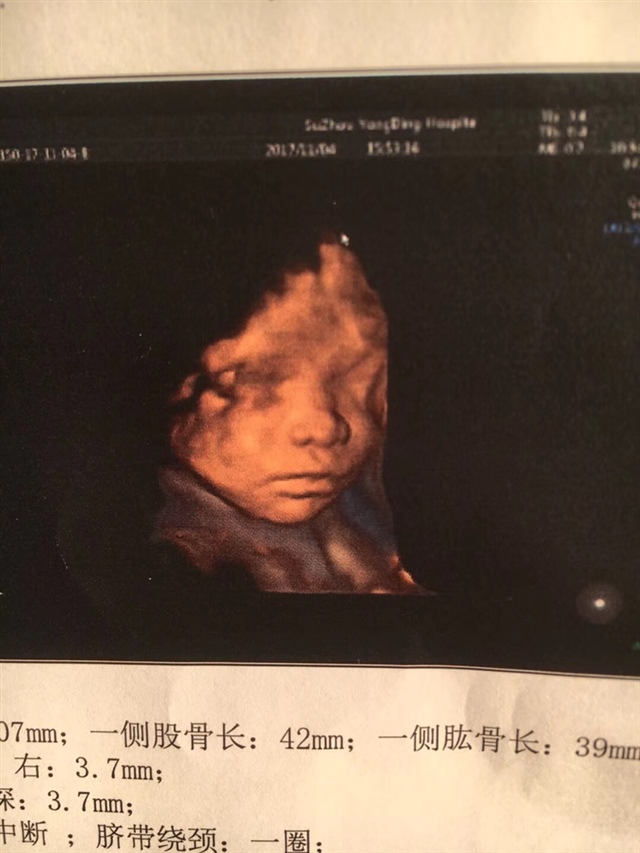

孕26周+1天

从胎心率上来看应该是女孩,我家儿子137,这胎已知女儿147,也看了几张别人的,大概率是女生